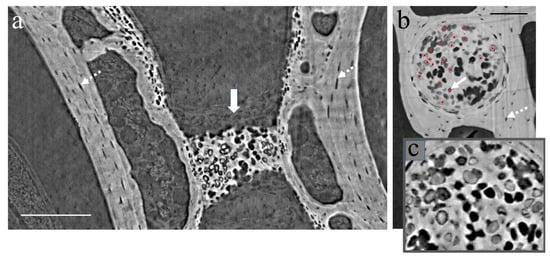

3.1. XPCT Experimental Results and 3D Visualization

3.2. The Vertebrae and Notochord 3D Analysis